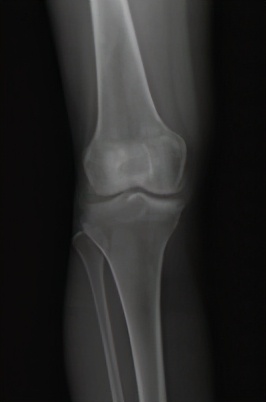

图1 膝骨关节炎x片表现:a早期

图1 膝骨关节炎x片表现:b中期

图1 膝骨关节炎x片表现:c晚期

膝骨关节炎的早期表现为膝关节疼痛,随着病情进展,会出现疼痛加重并活动受限,关节畸形。患了膝骨关节炎该如何治疗?首先需明确, 治疗的目的主要是2个,即解决疼痛,改善关节功能。 解决了这两个问题,最终就会实现生活质量的提高。那么如何缓解疼痛?怎样改善功能?这是每个膝骨关节炎患者最关心的问题,这需要根据病情的严重程度,采取个体化的治疗手段。患者希望以最小的代价获得最满意的疗效,这也是医生不竭的医术追求。